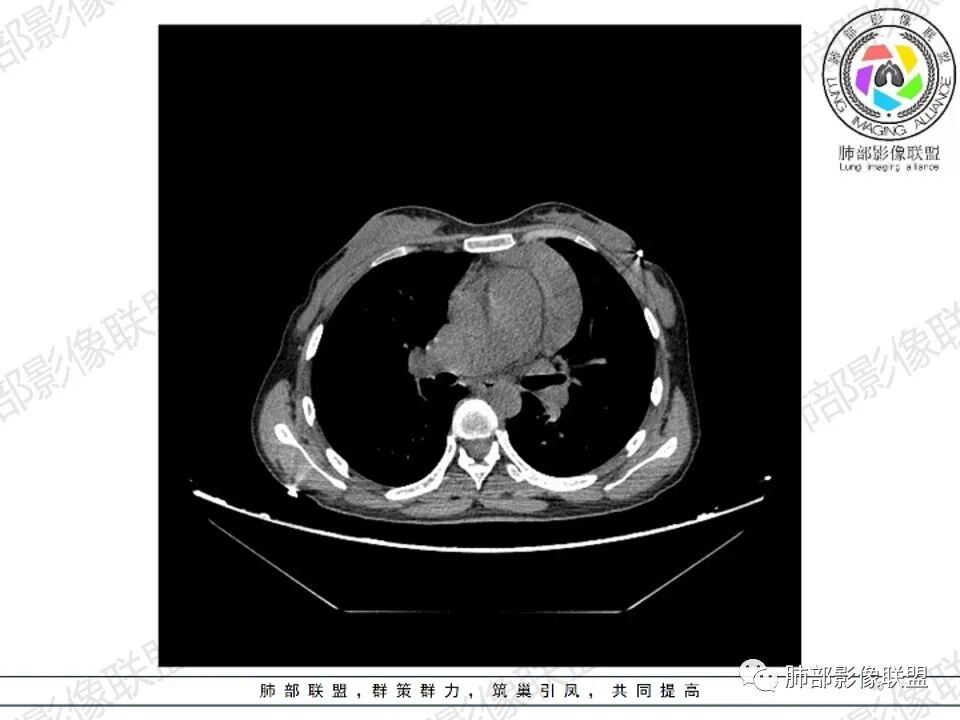

女,27,间断头晕、乏力3年,左眼视物模糊2月。贫血。胸部CT:前纵隔不规则肿块,多结节融合,边界不清,沿主动脉及肺动脉间隙生长,平扫密度欠均匀,增强扫描可见多发低密度坏死,纵隔血管供血穿行,腋窝多发大小不等淋巴结肿大。考虑恶性病变,胸腺癌?肉瘤?淋巴瘤?鉴别胸腺瘤、结节病等。

2.影像显示前纵隔不规则块状影,依势贴附心脏大血管旁,密度不均,边界不甚清楚,有结节融合感。

3.病灶轻度不均匀强化,可见血管穿行,散在液性低密度区。

双肺门未见肿大淋巴结。

4.双侧腋窝区见增大淋巴结,边界清楚。

1.年轻女性,前纵隔不规则块状影,密度不均,边界不甚清楚,有结节融合感,轻度不均匀强化,可见血管穿行,最常见最符合的无疑是淋巴瘤!